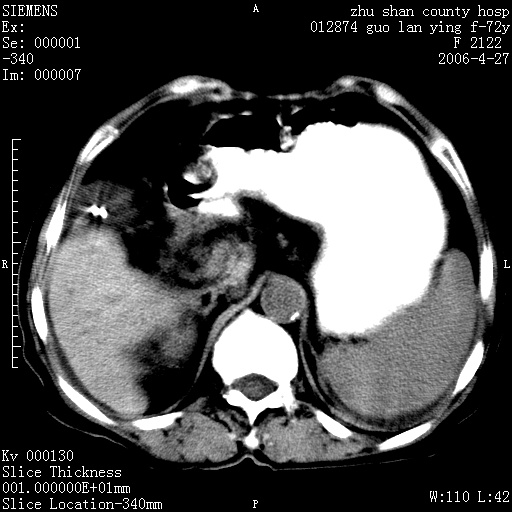

平扫所见:胆囊区两点壮高密度影,灶周有伪影{请问楼主患者有手术病史?}。肝实质内未见明显异常{建议强化或mri}.腹腔有少量积液,脾明显增大.右肾形态似不规则?

腹腔内示积液征,脾脏略增大,肝脏由于运动伪影较多,影响观察,内未见明显高密度区,胆囊内示两处高密度结石。胃窦部壁轻度增厚。另外,肝脏的前缘似有游历气体。不知病人的临床如何?有必要做胃的检查,还有,看看骨窗是否有腹腔游离气体还是肠管影响的。

肝脏缩小,脾脏增大,肝脾外缘及胆囊窝液性密度影,肝脾ct值正常,胆囊区见两个类圆形高密度影,下腔静脉前方类圆形软组织密度影为肝脏岛叶,胃幽门区见软组织密度影,十二指肠钡剂充盈不好.

1:腹水2:胆囊结石3肝硬化?(不确定,请结合临床)4幽门区占位?(建议胃肠透视)

肝硬化,脾大,少量腹水

肝硬化、腹水、脾大,胆囊结石可以肯定。只是肝右叶两个低密度有必要增强确定一下;排除小肝癌。